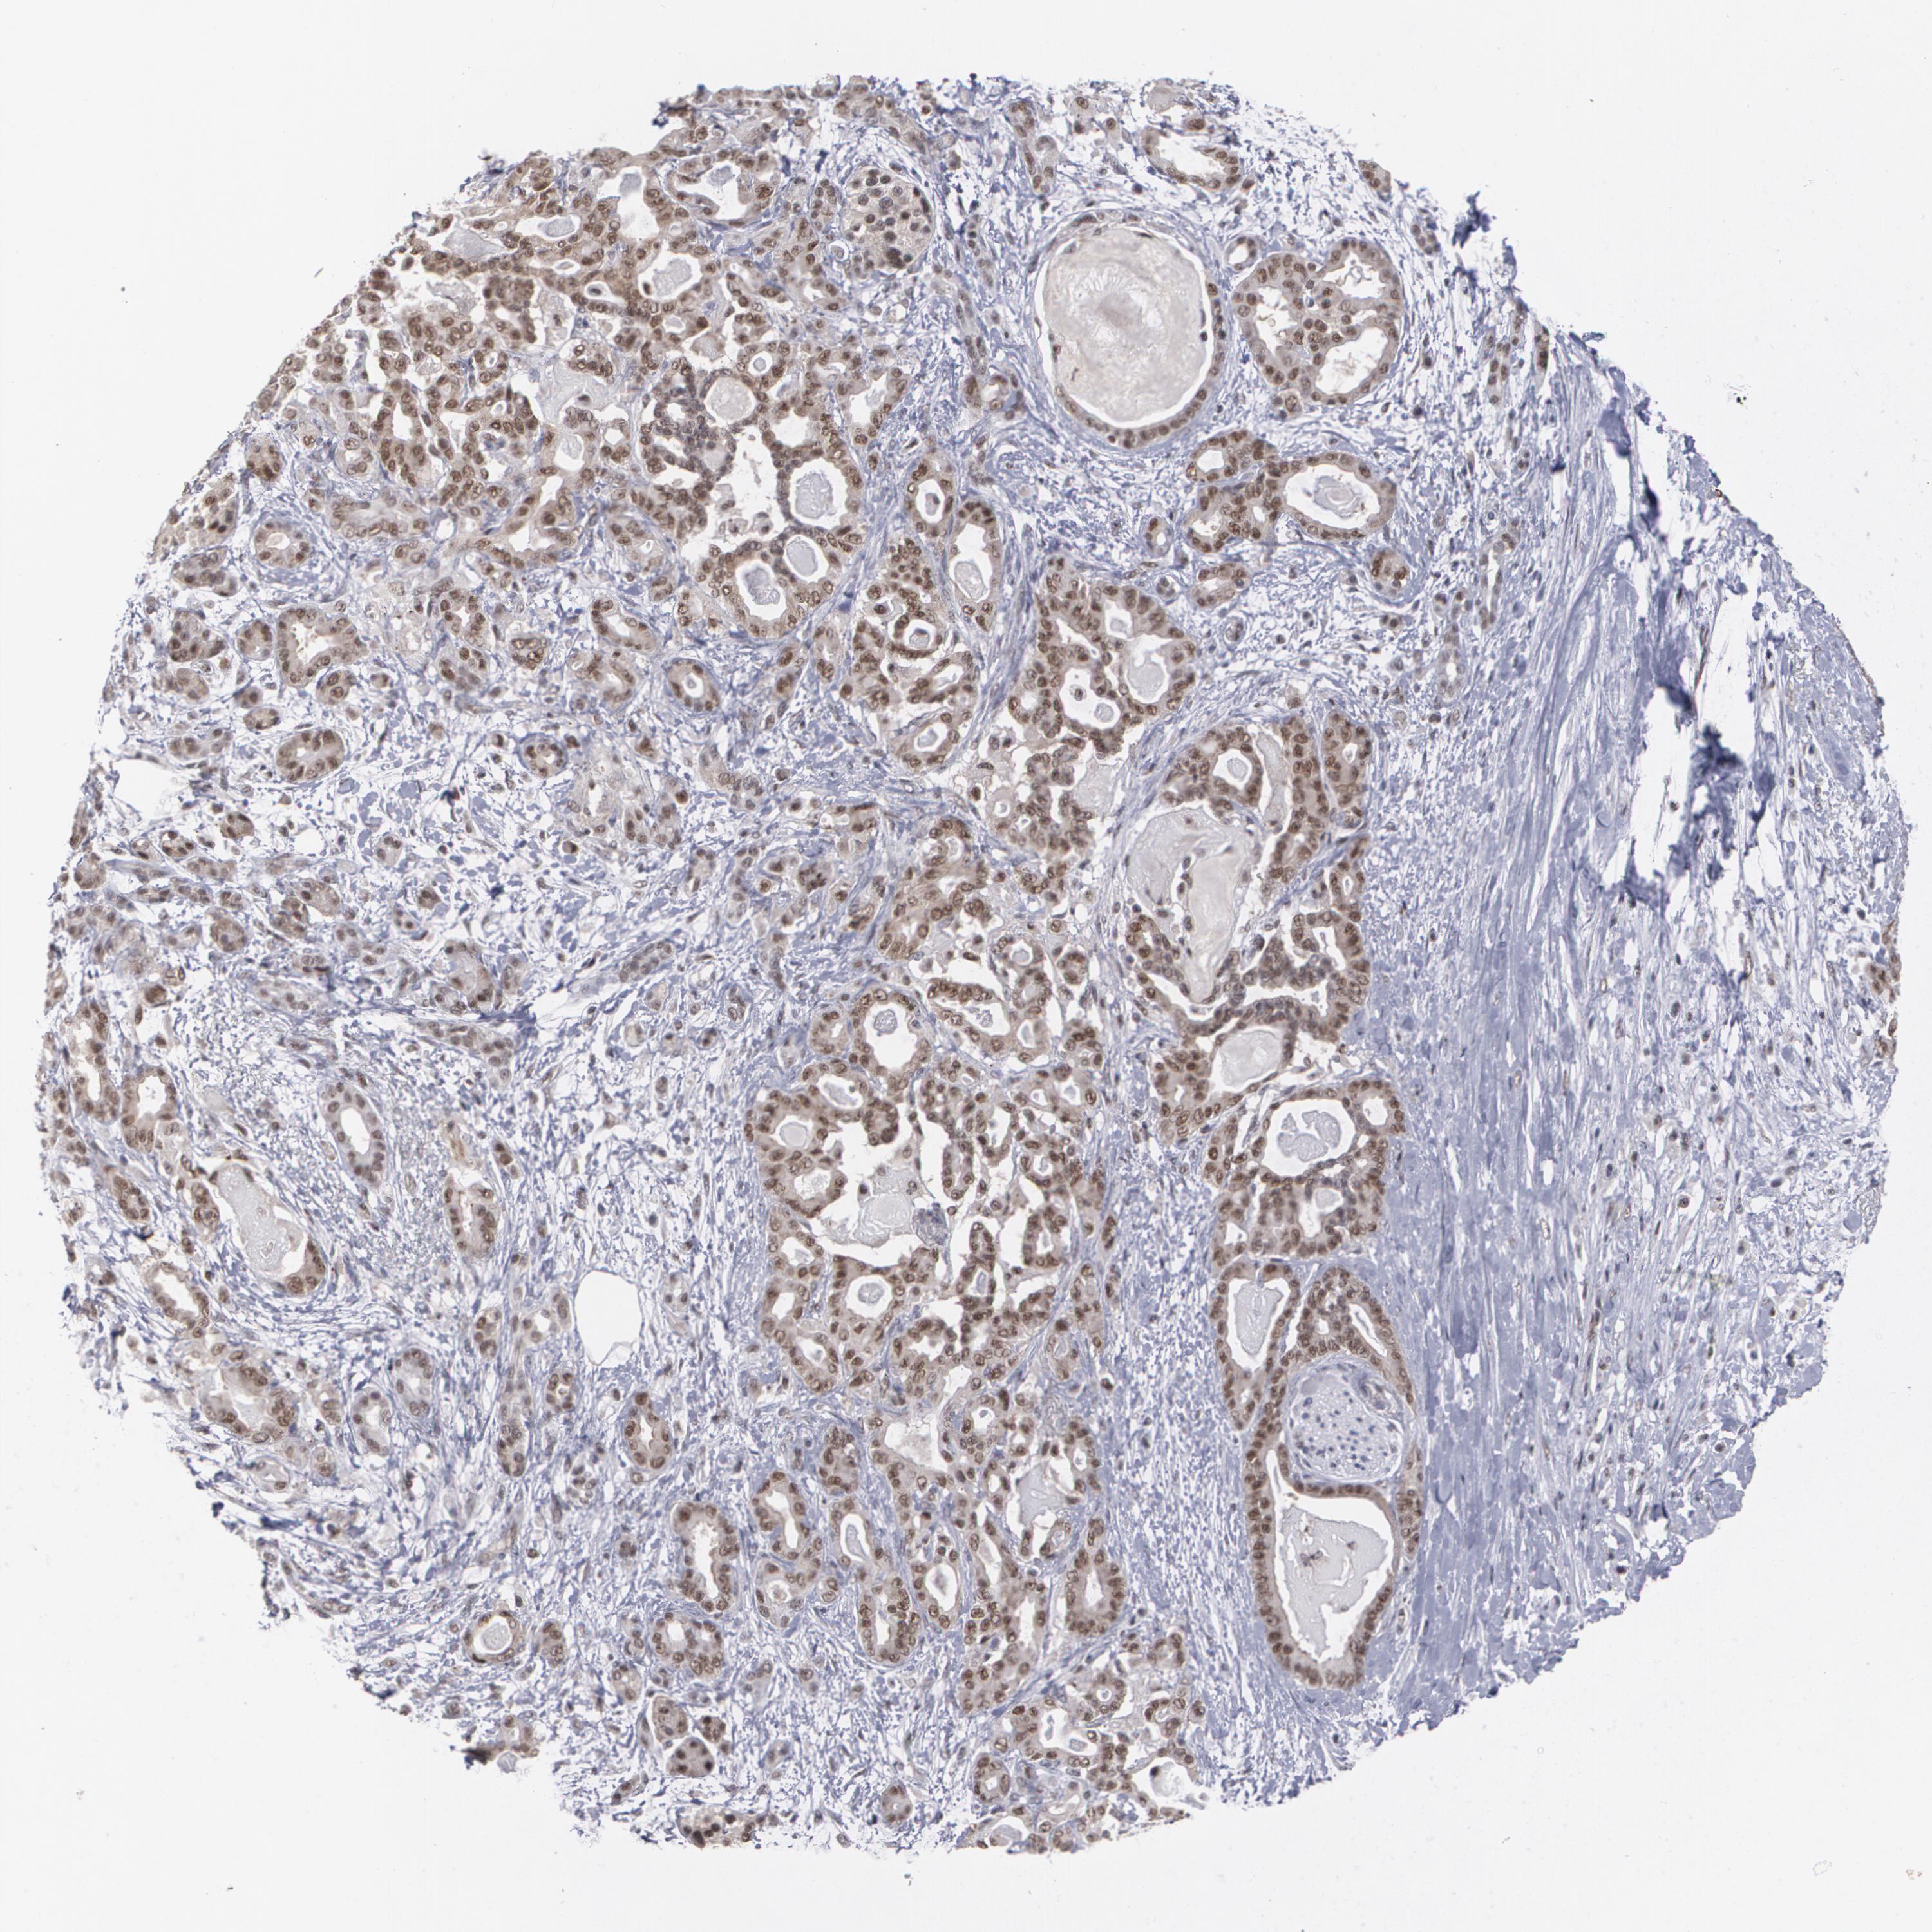

PANCREATIC CANCER - Protein expressioni

A mouse-over function shows sample information and annotation data. Click on an image to view it in a full screen mode. Samples can be filtered based on level of antibody staining by selecting one or several of the following categories: high, medium, low and not detected. The assay and annotation is described here.

Note that samples used for immunohistochemistry by the Human Protein Atlas do not correspond to samples in the TCGA dataset.

Antibody stainingi

Antibody staining in the annotated cell types in the current human tissue is reported as not detected, low, medium, or high, based on conventional immunohistochemistry profiling in selected tissues. This score is based on the combination of the staining intensity and fraction of stained cells.

Each image is clickable and will lead to virtual microscopy that enables deeper exploration of all samples and also displays staining intensity scores, fraction scores and subcellular localization as well as patient and tissue information for each sample.

Antibody HPA001552

Antibody HPA013335

Staining

High

Medium

Low

Not detected

Intensity

Strong

Moderate

Weak

Negative

Quantity

>75%

75%-25%

<25%

None

Location

Nuclear

Cytoplasmic/membranous

Cytoplasmic/membranous,nuclear

Adenocarcinoma, NOS

Adenocarcinoma, metastatic, NOS